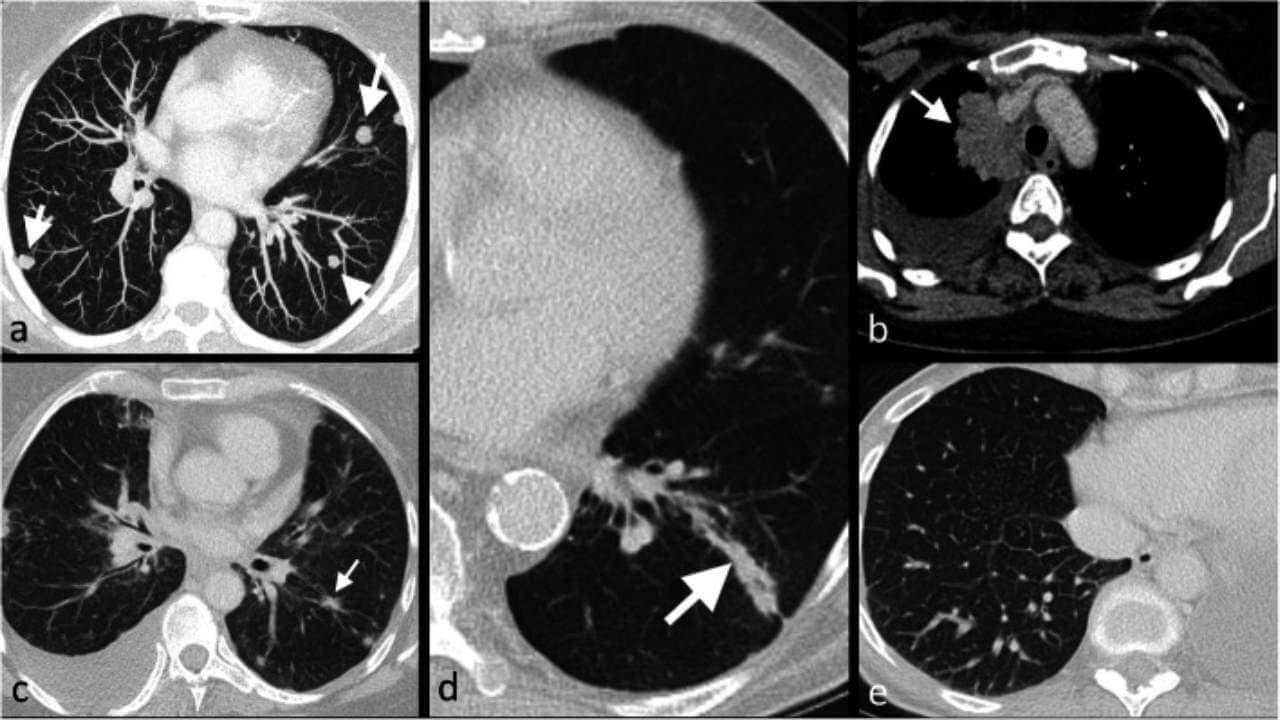

نقائل الرئة ليست سرطان الرئة بل تتكون من خلايا سرطان الثدي النقيلي. وتظهر غالباً على شكل عُقيدات متعددة بأحجام مختلفة، أو في حالات أقل شيوعاً على شكل عُقيدة رئوية منفردة (عُقيدة واحدة). وعادةً ما تكون بدون أعراض ويتم اكتشافها أثناء التصوير المقطعي المحوسب للصدر CT.

عند الاشتباه في وجود نقائل الرئة، يُطلَب عادةً إجراء التصوير المقطعي المحوسب للصدر CT أو التصوير المقطعي بالإصدار البوزيتروني PET. إذا كشف التصوير عن وجود ورم وأكد الطبيب أنه سرطاني، فمن المهم أيضاً تحديد ما إذا كان سرطان رئة أولي - أي سرطان بدأ في الرئتين - أو سرطان ثدي انتشر إلى الرئتين. يختلف علاج سرطان الرئة الأولي عن علاج سرطان الثدي النقيلي الذي انتشر إلى الرئتين.

تشمل أدوات التشخيص CT و PET-CT و MRI (في حالات مُختارة)، والخزعة (إذا لزم الأمر لتوضيح التشخيص)، والاختبارات الجينية الجزيئية، وعلامات الأورام، والاختبارات المناعية الكيميائية النسيجية.